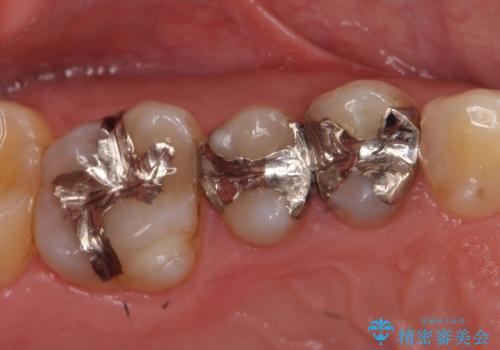

- 右上の銀歯を白くしたいといらっしゃった方の症例です。

右上4、5番目の歯はオールセラミッククラウンによる補綴、6番目の歯はセラミックインレーによる修復を行いました。